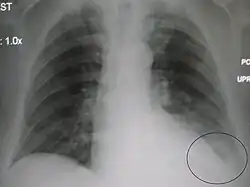

AP CXR showing left lower lobe pneumonia associated with a small left sided pleural effusion -

AP CXR showing right lower lobe pneumonia -

AP CXR showing pneumonia of the lingula of the left lung -

Right upper lobe pneumonia as marked by the circle. -

Left upper lobe pneumonia with a small pleural effusion.